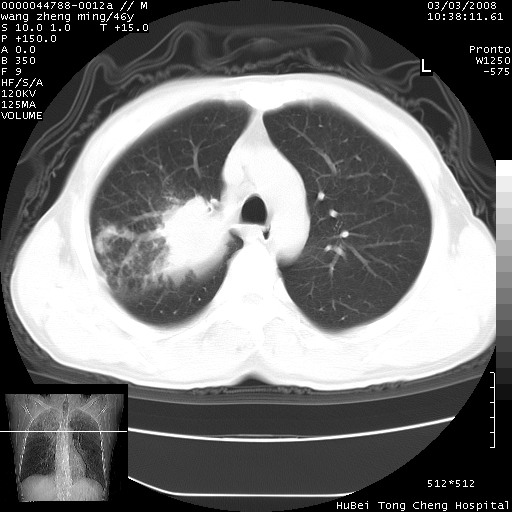

以下是引用卜一在2008-3-22 1:37:00的发言:[br]右肺实质性肿块,边缘不整,明显见毛刺征 分叶征及胸膜凹陷征,右上叶支气管明显变窄,远端散在的片状 斑片状实变影。另:左肺门较大肿块,支气管受累 变窄,远侧见阻塞性肺炎。纵隔内见肿大淋巴结。多考虑:右肺周围性肺癌伴左肺门 纵隔淋巴结转移!